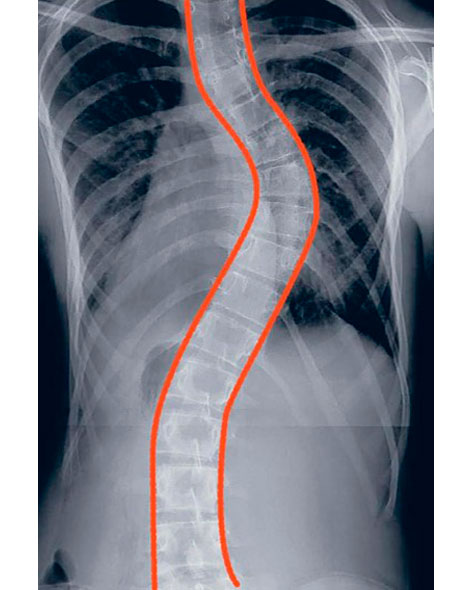

¿CÓMO SE VE LA ESCOLIOSIS EN LA RADIOGRAFÍA?